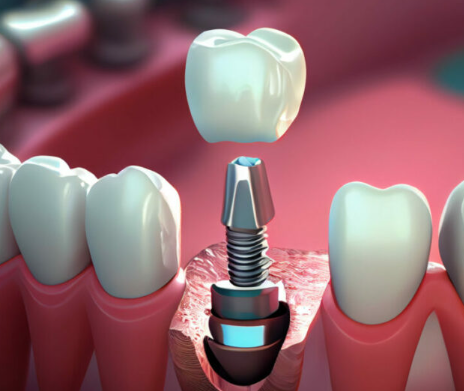

種牙係宜家修復缺牙最先進的方式,因此,有很多顧客會糾結種牙技術的選擇,那麼與傳統種牙相比,3D數字微創種牙技術有咩區別同優勢呢?

1、精確種植,提高成功率。

借助3D數字列印技術製作導板,準確定點、定深、定方向植入;植入種植體採用三維虛擬模型設計,避免重要結構位置,通過現有骨量優化植體位置。

2、種植快速高效,時間相對縮短50%。

種植體可以通過小切口植入,擺脫傳統種植方式的切口、翻瓣、縫合、拆線等步驟;種植速度同效率大大提高,種植時間比傳統種植時間短。

3.、微創種植大大提高了舒適度。

傳統的種植手術時間長,過程複雜,長期的手術往往會帶來身心不適;而數字種植手術採用微創技術,傷口小,時間短,顧客可以喺舒適、輕鬆的狀態下完成種植。

4、術中及術後併發症的概率降低。

通過喺電腦上創建三維虛擬模型,數字種植技術可以模擬種植體更好的植入方式;植入時避免了血管、神經等重要的結構位置;有效避免植入不當造成的神經創傷或穿透鼻竇腔。